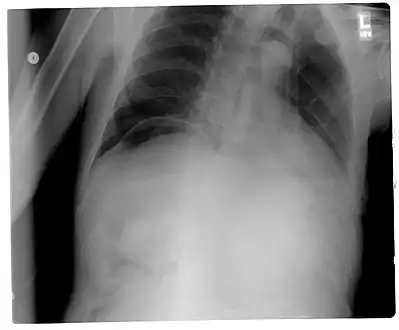

Chest X-ray with air between the right diaphragm and the liver (green and red arrows). Air also visible below the diaphragm on the persons left. Blue arrows mark a normal gas filled colon.